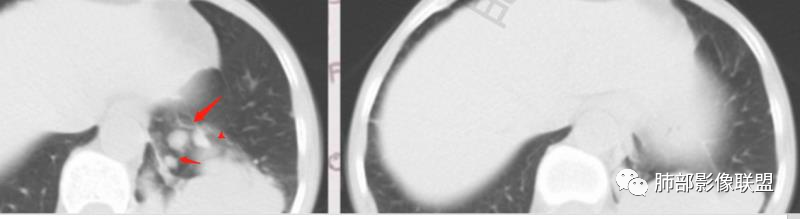

晨读:左肺下叶实性肿块,边缘光滑膨隆,近端支气管堵塞,远端宽基底与胸膜相连,部分胸膜下间隙消失,大肿块周围伴有多发小结节,小结节边缘光滑,平扫密度均匀,增强后不均匀强化,部分可见富血供强化,右肺下叶胸膜下条形实变影,收缩,右肺可能炎性病变,左肺下叶恶性肿瘤(癌肉瘤,肉瘤,鳞癌)

晨读:左肺下叶囊性肿块,边缘光滑膨隆,近端支气管堵塞,临近肺呈受压改变,与胸膜平行,近端多发小结节,小结节边缘光滑,似见轻度强化,血管贴边,内见分隔,考虑良性病变,支气管源性囊肿,结核或隐球

晨读:中年女性,无症状。胸部CT:左下肺后基底段肿块样病灶,边界清楚,患侧肺体积有减小。边缘光滑,囊性为主,可见分隔,相应肺段支气管未见,邻近肺受压,增强扫描强化不明显,仅有局部边缘强化,可能为支气管壁。个别层面似有肺外血管穿入。周围有散在小结节,形态、边缘、密度、强化一致。右下叶前基底段索条影。

考虑:支气管囊肿>肺隔离>CPAM>TB,鉴别Ca。